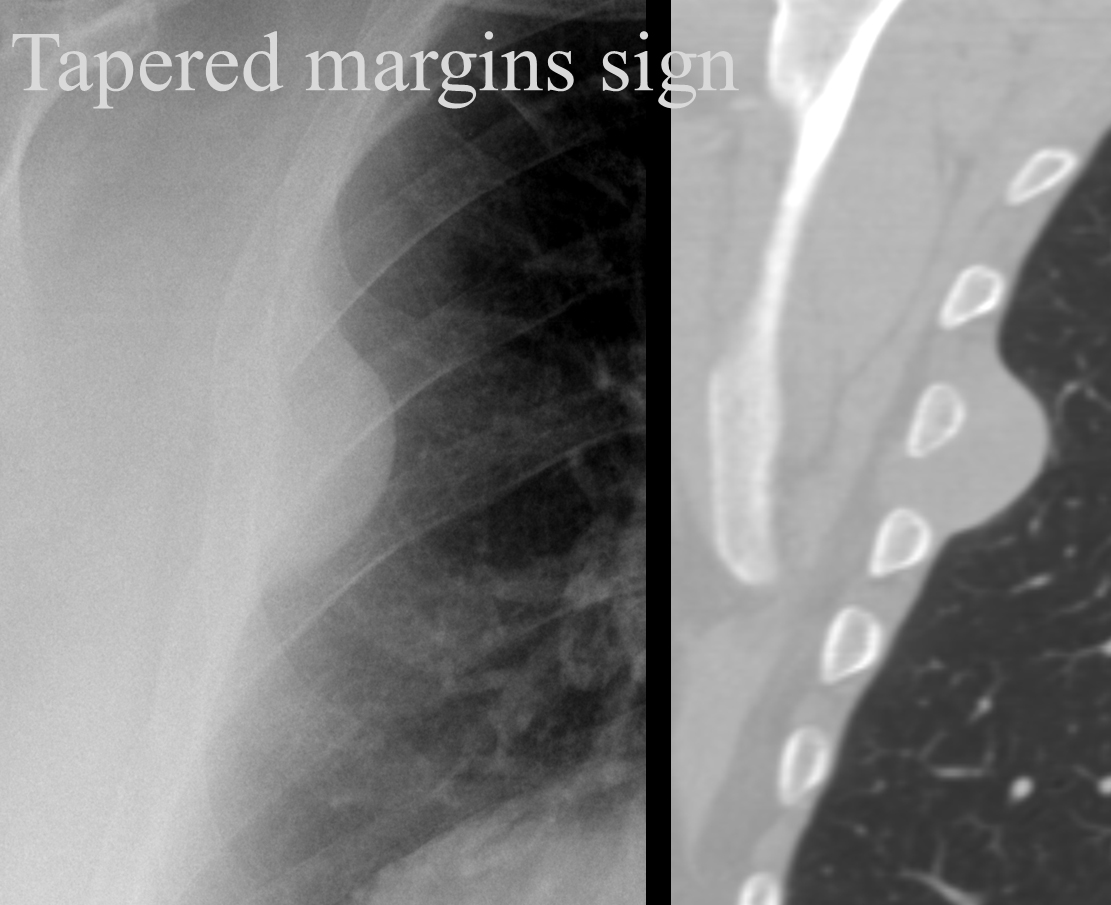

Tapered margins sign

Pleural or extrapleural origin